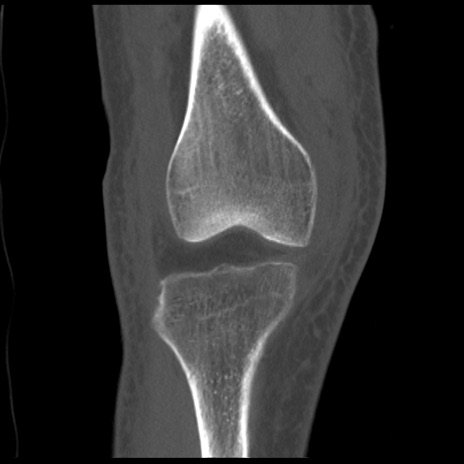

症例28 右膝関節CT(冠状断像)

右膝関節CT